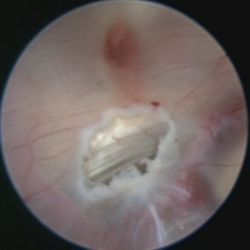

Das hierfür verwendete Verfahren ist die endoskopische Ventrikulozisternostomie (englisch endoscopic third ventriculostomy = ETV). Hierbei wird ein feines Endoskop in die erweiterten Hirnkammern vorgeschoben und damit am Boden des 3. Ventrikels in einem Areal, welches keine Funktion enthält, unter Sicht meist mit einem Speziallaser eine Öffnung geschaffen.

Unter der Voraussetzung, dass das Hirnwasser aus den hier liegenden Hirnwasserräumen, den sogenannten „basalen Zisternen“, auch frei abfließen kann, und die o.g. Abflussbehinderung die einzige Ursache des Hydrocephalus darstellt, ist die ETV ein sehr elegantes und dann sehr erfolgreiches Verfahren.